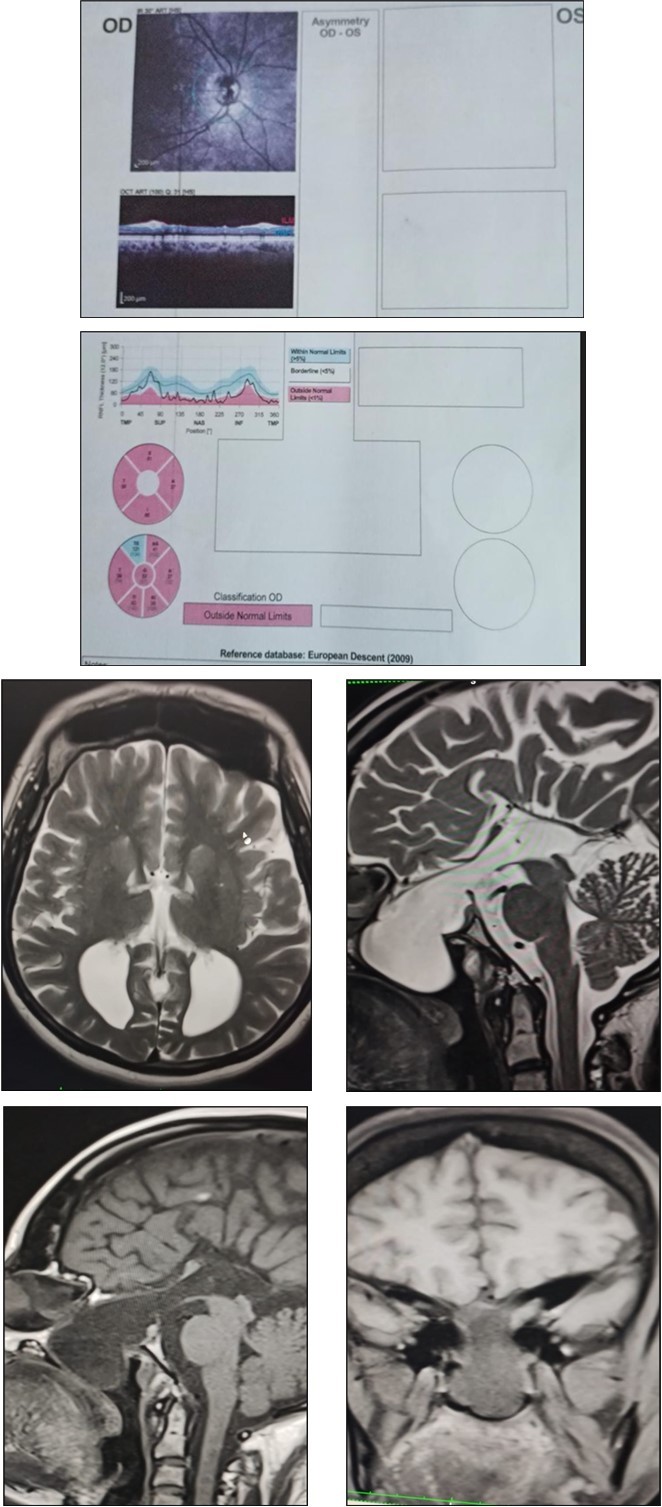

MRI showed parallel running lateral ventricles and colpocephaly (Racing Car appearance), large central sphenoethmoidal meningoencephalocoele with large bony defect in anterior sellar floor, planum sphenoidale and ethmoid bone. Herniated sac (4.1x3.5x2.6) contains bilateral optic nerves olfactory nerves, infundibulum of pituitary gland and csf. Pthisis bulbi of left eye noted.Figure 1

Figure 1.Fundus Images and OCT – right optic atrophy ; pale optic disc